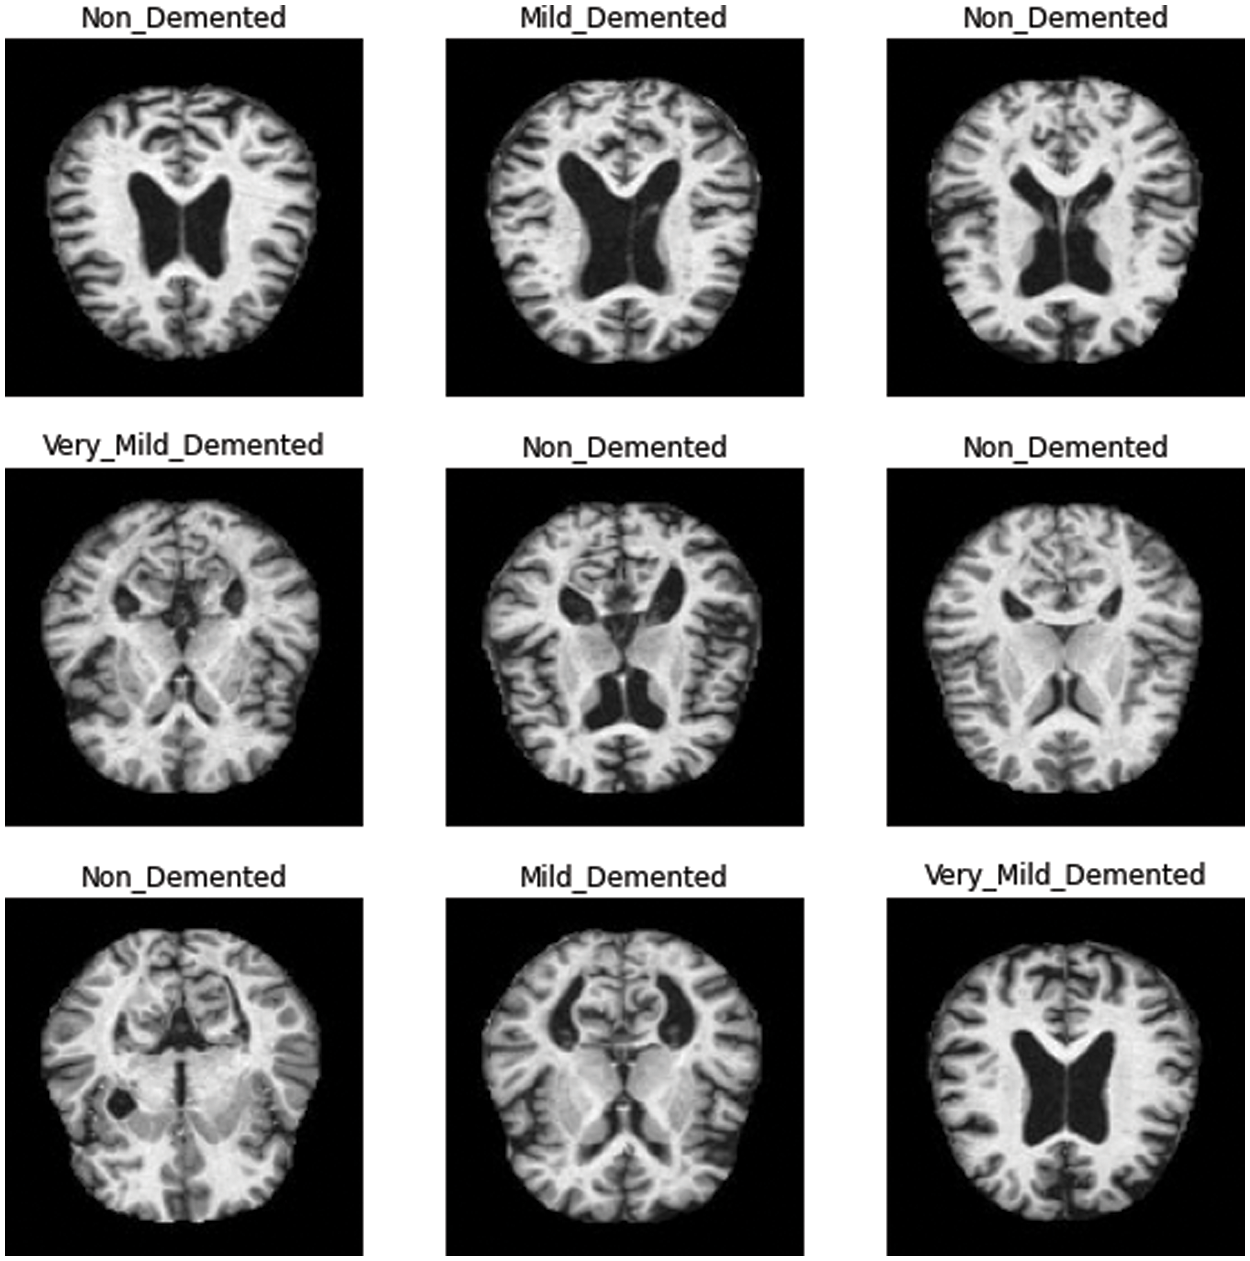

The Alzheimer’s brain MRI dataset of 6400 images was collected from Kaggle [28]. The dataset was divided into four different classes: mildly demented, moderately demented, non-demented, and very mildly demented. The number of images per class were of variable length in that mildly demented contained 896, moderately demented contained 64, non-demented contained 3200, and very mildly demented contained 2240 images, which comes to a total of 6400 images, as shown in Fig. 1. The dataset was processed with all images resized into (128 × 128) pixels. Fig. 2 shows sample images of the Alzheimer’s dataset displayed from the training set.

Figure 2: Sample images in training set